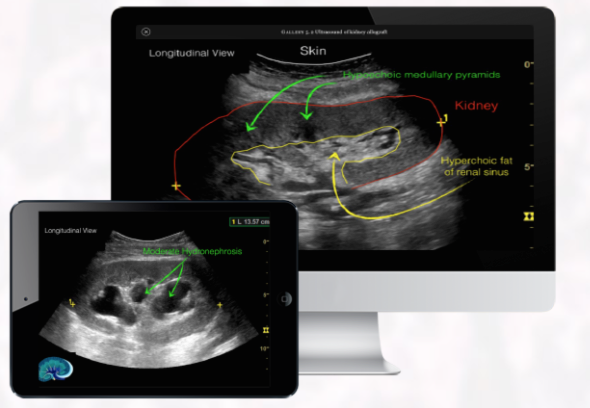

Ultrasound is another area where fellows really ought to learn more during their fellowship, since I am confident that performing a bedside ultrasound can significantly improve patient care by identifying earlier abnormalities such as an obstruction or a lack of blood flow in kidney grafts. Ultrasound books made by radiologists are also over detailed for the fellow and are rarely used in practice.

To overcome the above limitations, I have been working for the past 6 years in an interactive transplant learning tool that contains more than 300 original figures/illustrations, questions, key-points and videos to consolidate all aspects of transplantation in one place. Helmut and Vanesa have provided me with slides from all kidney transplant patients that I have attended on, allowing me to share individual cases with beautiful biopsy findings.

It was a lot of work since I decided to do all by myself, including illustrations, collection of radiology images, videos, graphs, questions,… The goal was really to have a book with a consistent approach to topics and similar style through out. This would be impossible if I had invited multiple contributors… Videos were elaborated to explain difficult topics such as anti-HLA assays, and problem-based cases describe the thought processes, differential diagnosis and management of common conditions affecting kidney transplant recipients. Lastly, questions and review key-points on every chapter will test the reader’s knowledge and hyperklinks will allow direct access with one-click to key references on Pubmed. The end-product was just made available online two weeks ago.